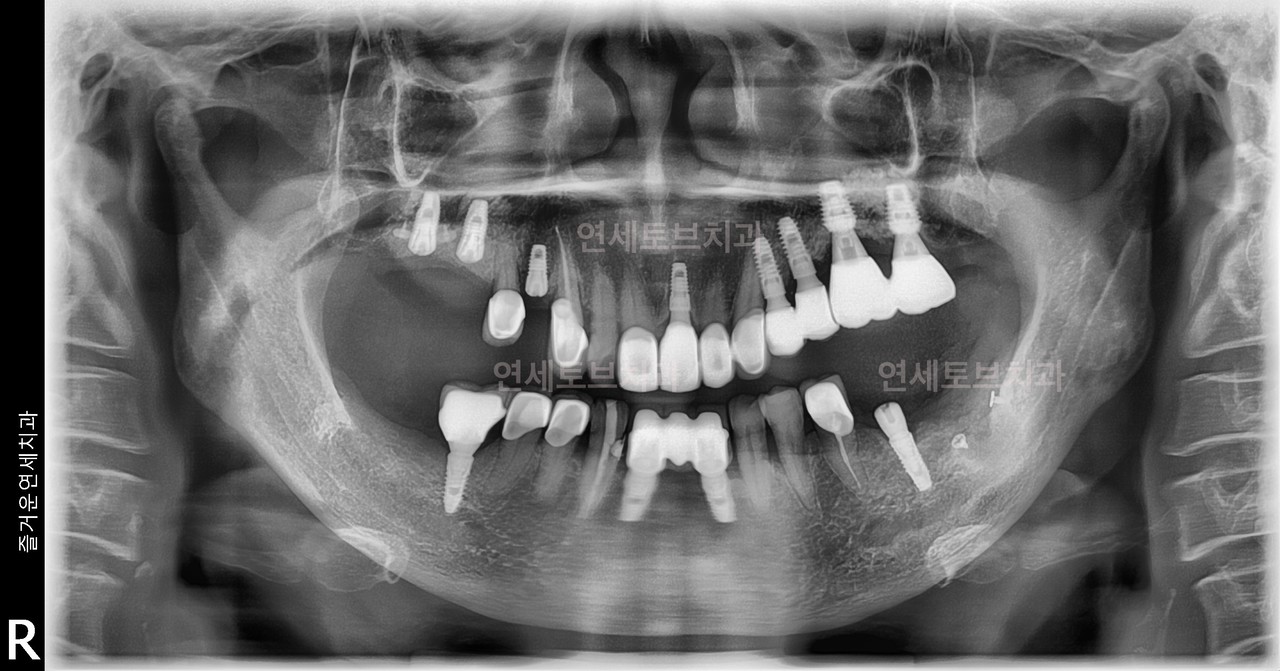

기존에 식립한 임플란트에 문제가 발생했을 때 이를 다시 치료하거나 교체하는 과정을 말합니다.

임플란트는 반영구적으로 사용할 수 있지만, 다양한 원인(잇몸뼈 흡수, 임플란트 주위염, 보철물 파손, 식립 위치 오류 등)으로 인해 재치료가 필요할 수 있습니다

기존에 식립한 임플란트에 문제가 발생했을 때 이를 다시 치료하거나 교체하는 과정을 말합니다. 임플란트는 반영구적으로 사용할 수 있지만, 다양한 원인(잇몸뼈 흡수, 임플란트 주위염, 보철물 파손, 식립 위치 오류 등)으로 인해 재치료가 필요할 수 있습니다